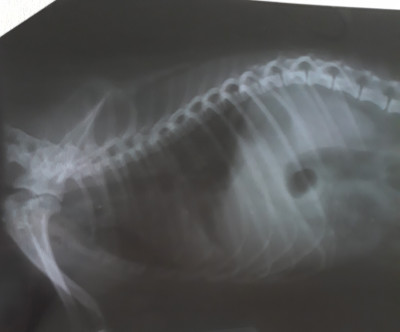

Только вернулись домой. Через час снова в клинику... Снимки пока не расшифровали,но мне кажется все плохо на них((( чуть позже выложу фото, может быть кто-то подскажет что-то...

Вот снимки...

Я не рентгенолог, конечно, но отчетливых признаков отека не вижу. Смущает состояние левого легкого, затенение верхней и средней доли.

Качество снимков еще не очень.

Ну, подождём заключение специалиста.